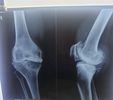

Fracture Treatment in Kolkata: What to Do in the First 24 Hours

I have seen some of the most complicated and dangerous fracture cases in the past 10+ years. Thus, I always recommend getting fracture treatment as early as possible to prevent serious complications.